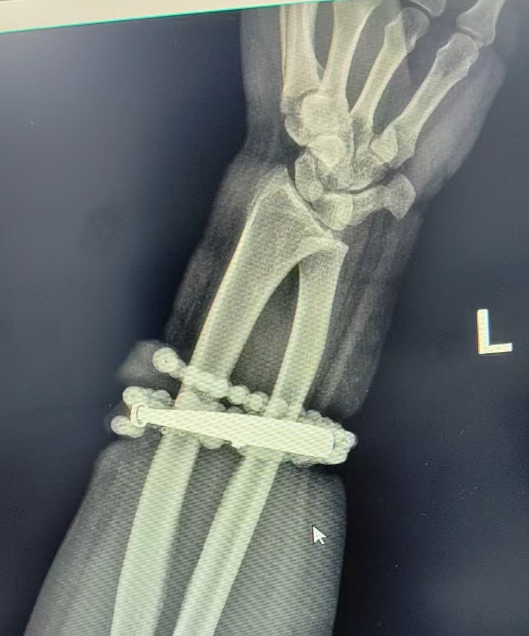

然而,就在兩週前,龔女士的情況急轉直下:手腕不僅疼痛加劇,還出現了明顯的紅腫,甚至有膿液滲出。她這才驚覺——手鐲和串珠,已經有一部分“長”進了肉裏,根本取不下來了!

“這是典型的首飾長期壓迫、摩擦,加上細菌感染,引發的慢性炎症和肉芽組織增生。”醫生介紹,此時,手鐲和串珠已經成了一個不斷刺激皮膚、污染傷口的“病竈”,如果不盡快手術取出,感染可能進一步擴散,甚至危及生命或影響手臂功能。

經過一個多小時的手術,醫生們將手鐲和串珠從厚厚的增生組織中完整剝離出來。目前,龔女士恢復良好,已順利出院。